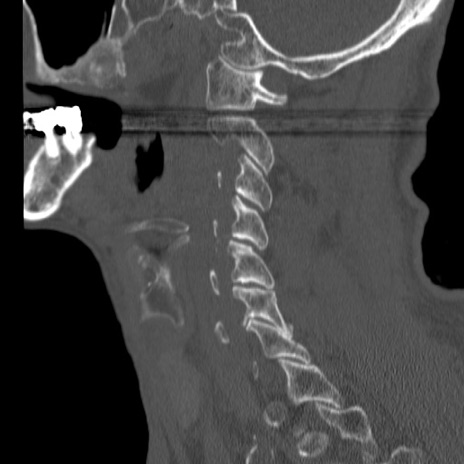

症例46 頚椎CT(矢状断像)

【症例】80歳代男性

【主訴】両側頚部〜上肢のしびれ

【現病歴】昨日、自宅内で転倒、その後より上記症状あり。意識障害なし。

【身体所見】両側上肢のallodynia(熱痛覚過敏)あり。MMTおよびDTRは正確な所見取れず。両上肢の挙上はなんとか可能。

異常所見と診断は?